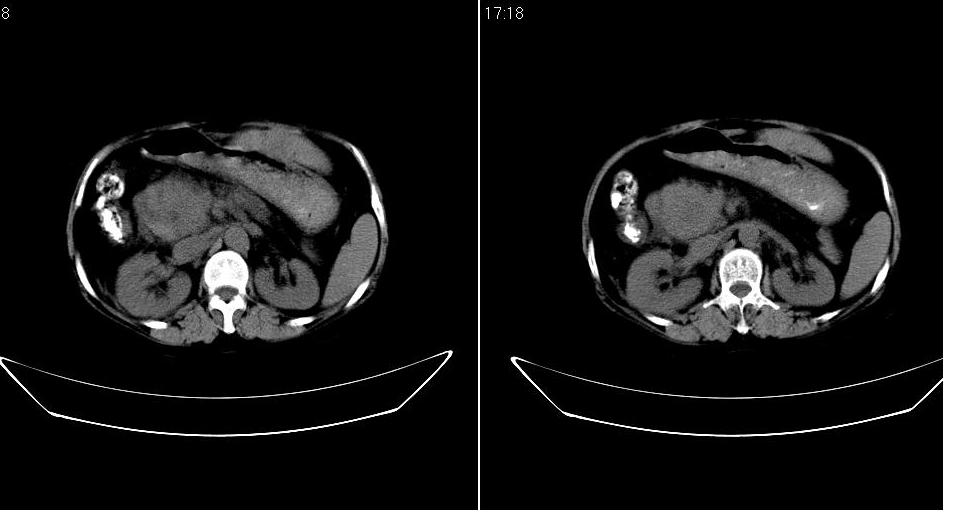

以下是引用守望可可西里在2007-1-20 23:09:00的发言:[br][br] 胰头癌,胆总管梗阻、截断,肝内外胆管重度扩张,肝内边缘部分的圆形低密度病灶多能与扩张的胆管较为连续,暂不考虑转移。病人没有黄疸吗?

以下是引用天南地北在2007-1-20 23:22:00的发言:[br]1:按照肿块的位置及胆总管的形态:考虑胆总管(中下段)癌并肝内胆管扩张,累及胰头。2:不排除胰头癌并肝内胆管扩张。[br]肝内病灶看起来还是扩张的胆管,不考虑转移先。